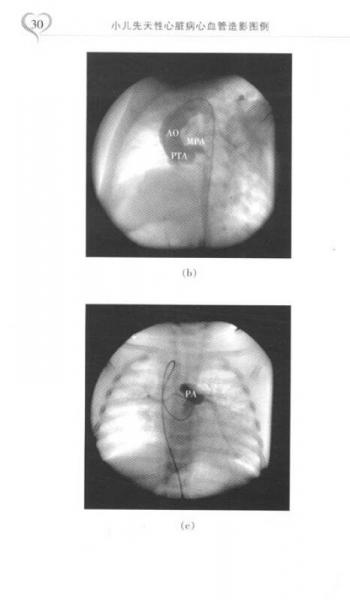

小儿先天性心脏病心血管造影图例

《小儿先天性心脏病心血管造影图例》共分4章,主要内容有:左向右分流型先天性心脏病、右心发育异常类先天性心脏病、左心发育异常类先天性心脏病以及房-室和室-大动脉连接异常。本书以复旦大学附属儿科医院心血管中心3000多例先天性心脏血管病心血管造影实例图像为基础,配以注解,介绍先天性心脏血管病的心血管造影诊断,病种以及图像资料比较齐全。《小儿先天性心脏病心血管造影图例》是一本易读易懂并有较强实用价值的专业书籍。作者系复旦大学附属儿科医院教授。